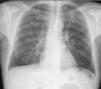

Presentamos el caso de un varón de 56 años, ganadero, con antecedentes personales de enolismo, que consultó por dolor lumbar de 2 meses de evolución. Por este motivo se realizó un estudio mediante radiología simple y resonancia magnética nuclear que puso de manifiesto una espondilodiscitis D12-L1. El análisis de sangre mostró una anemia de trastornos crónicos y las serologías para VIH y brucela fueron negativas. La prueba de Mantoux fue de 10mm. La radiografía de tórax mostraba tractos fibrocicatriciales de predominio en el lóbulo superior izquierdo y una lesión nodular compatible con un granuloma no calcificado en el lóbulo superior derecho (fig. 1).